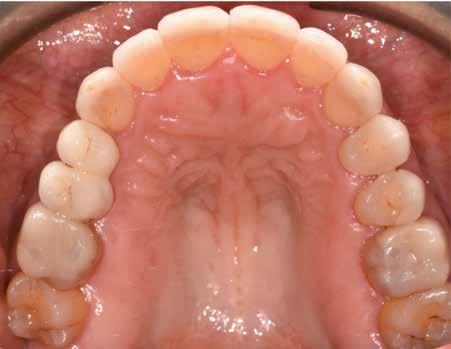

A fogazat elhasználódása alatt azoknak a degeneratív folyamatoknak az összesített hatását értjük, melyeken az élet során a szervezet keresztülmegy. Ezek lehetnek a fogérintkezések közben fellépő mechanikai erők (abrázió, attríció), endogén vagy exogén eredetű savas közegek által kiváltott kémiai behatások (erózió), kariogén baktériumok által okozott pathológiás folyamatok és parodontális elváltozások, valamint iatrogén ártalmak.

A felnőtt páciensek kezelése során általában egyszerre több ellátásra szoruló elváltozást is diagnosztizálhatunk: hiányzó fogak, kopott fogazat, esetleg régi, nem megfelelő, sérült fogpótlások, rendellenes helyzetben lévő fogak stb… Ezen páciensek kezelésekkel kapcsolatos kérései mindig az esztétikai vagy a rágással kapcsolatos kívánságaik kielégítését szolgálja. A kezelések során a fogorvosoknak nem csak a páciensek kéréseinek teljesítésére, hanem ezzel egyidejűleg a fogazat általános megjelenésének és funkciójának lehetőség szerinti javítására is törekedniük kell. Mindemellett a lehető legtöbb saját foganyag megőrzését és az évek során elvesztett kemény- és lágyrészek pótlását (pl.: hiányzó fogak, sorvadt állcsontgerinc, lágyszöveti defektusok) is szem előtt kell tartaniuk, úgy, hogy közben egy hosszú távon fenntartható eredményekkel járó kezelési tervet állítanak össze. Ezek mindig összetett esetek. Annak érdekében, hogy a fentiekben megfogalmazott összes kezelési célt teljesíteni tudjuk, interdiszciplináris megközelítésre van szükség. Az ilyen komplex rehabilitációs kezeléseket „fogászati megfiatalításnak” nevezzük. Ezeknek a beavatkozásoknak lényege az elhasználódott fogazat biológiai szempontokat figyelembe vevő minimál invazív módon történő helyreállításában rejlik, mely folyamat végére a páciensek fogai visszanyerhetik fiatalkori megjelenésüket.

A rehabilitációs kezeléseknek a célja, hogy a páciensek a lehető leghosszabb időn keresztül képesek legyenek mosolyogni és rágni. A protetikai kezeléseket végző fogorvosoknak helyre kell tudni állítaniuk a fogívek szabályos lefutását és az alsó és felső fogív között megfelelő interokkluzális érintkezéseket kell létrehozniuk. Így lehet csak az ellátás befejezését követően elért végeredmény biológiai szempontokat figyelembe vevő esztétikáját, funkcionális megfelelőségét, hosszú távú fenntarthatóságát biztosítani.

Nagyon fontos, hogy már a kezelések elején meghatározzuk, hogy melyek azok a hiányzó fogak, amelyeket a későbbiekben pótolni szeretnénk, valamint helyesen diagnosztizáljuk a kariológiai, endodonciai vagy parodontológiai okok miatt ellátást igénylő elváltozásokat. Szintén kiemelt jelentőséggel bír a fogak megtarthatóságának kiértékelése. A kezelési terv felállítása során tisztában kell lennünk azzal, hogy mely fogak alkalmasak fogpótlások ideiglenes vagy végleges elhorgonyzására.

A preprotetikai fázisban el kell látnunk a diagnosztizálásra került kórfolyamatokat, megfelelő pozícióba kell állítanunk a megtartani kívánt fogakat, pótolnunk kell az elvesztett csontállományt, valamint gondoskodnunk kell az íny megfelelő állapotáról. Ha szükség van rá, úgy a foghiányok pótlására szolgáló dentális implantátumok is ebben a fázisban kerülnek behelyezésre. Általánosságban elmondható, hogy azokat a kezeléseket, amelyek befejezése biológiai okok miatt hosszú időt vesz igénybe (pl.: fogszabályozás, csontpótlás, implantáció), a lehető leghamarabb érdemes elkezdeni.

A fogszabályzó kezelések egyik legfontosabb célja, hogy elérjük a lehető legharmonikusabb interokkluzális fogérintkezéseket, továbbá az állcsont relációs helyzetének frontális és szaggitális síkban is megfelelőnek kell lennie. A fogszabályzás befejezésekor a fogpozícióknak nem orthodonciai, hanem protetikai szempontok szerint kell ideálisnak lenniük. Az Invisalign ClinCheck szoftver (Align Technology) segítségével a protetikus az orthodontussal együtt meg tudja határozni azokat a végső fogpozíciókat, amelyek a lehető legjobb végeredmény biztosításához elengedhetetlenek. Bizonyos klinikai paramétereket, mint a fogak klinikai koronájának nagyságát, az egyes fogak fogíven belüli optimális pozícióját, a fogívek egymáshoz viszonyított helyzetét, a fogak között látható rések nagyságát, a frontfogak tengelyének dőlését, az overjet és overbite mértékét már a kezelések megkezdése előtt pontosan definiálni kell. Ezeket az adatokat viszont csak a tervezett végleges fogpótlás ismeretében lehet meghatározni, ezért van szükség az orthodontus és a protetikus szoros együttműködésére.